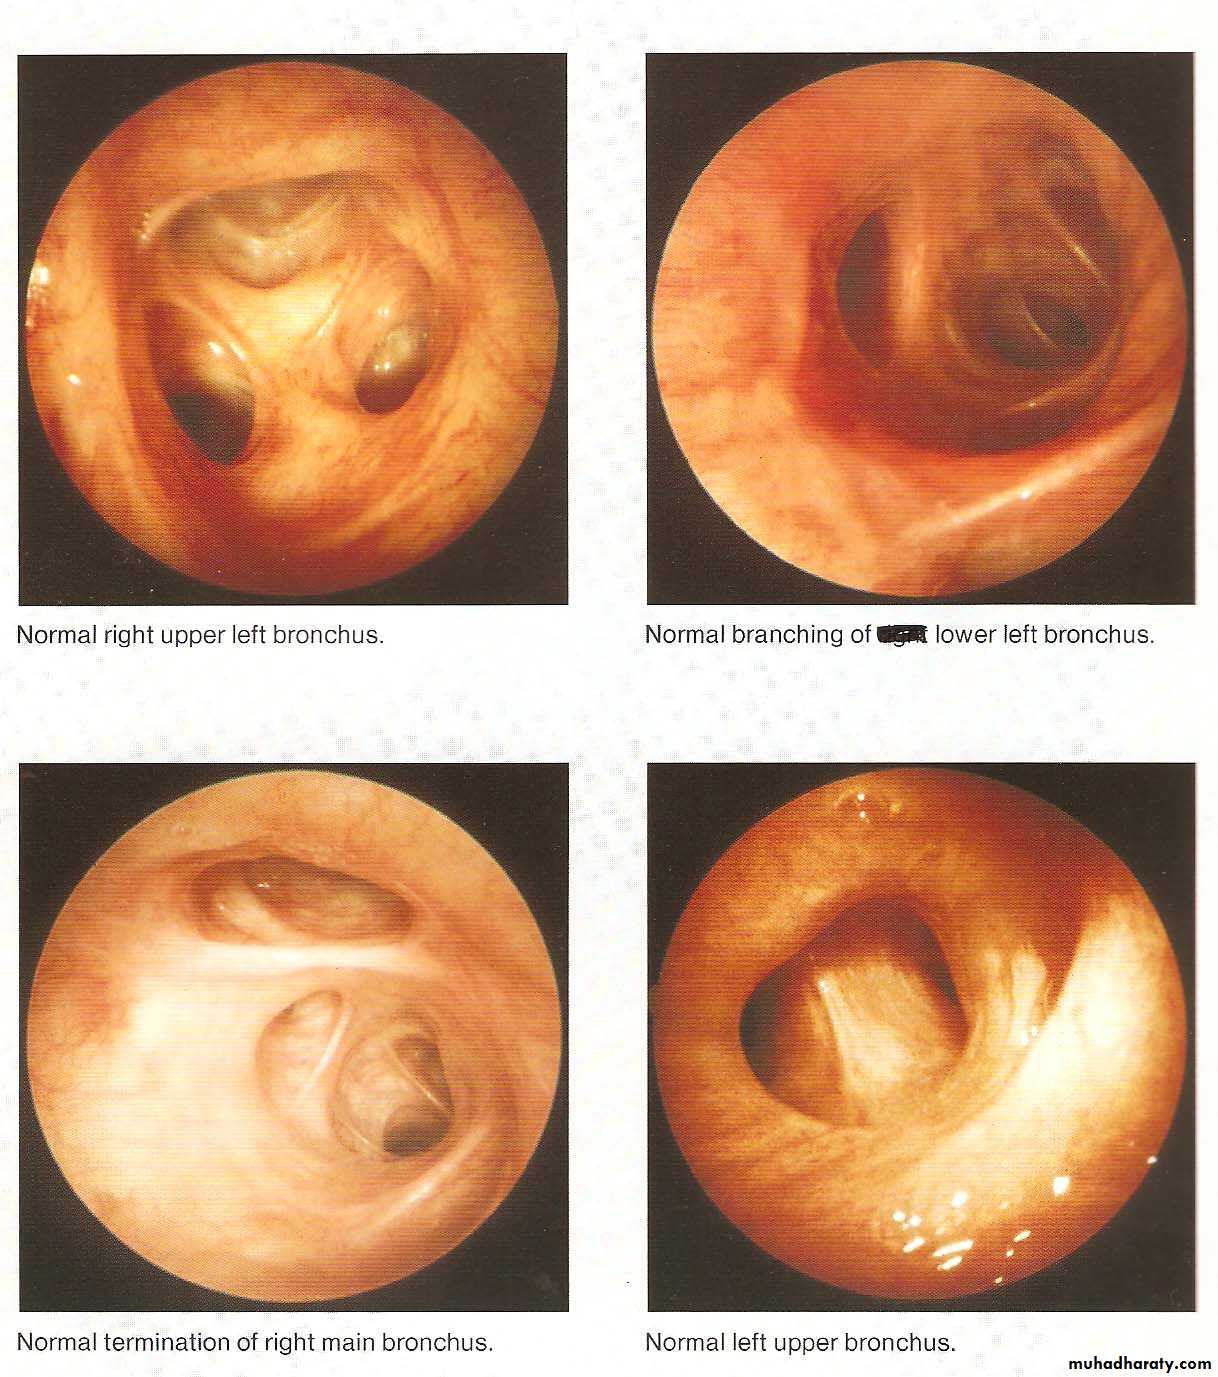

• Normal Bronchoscopic Findings